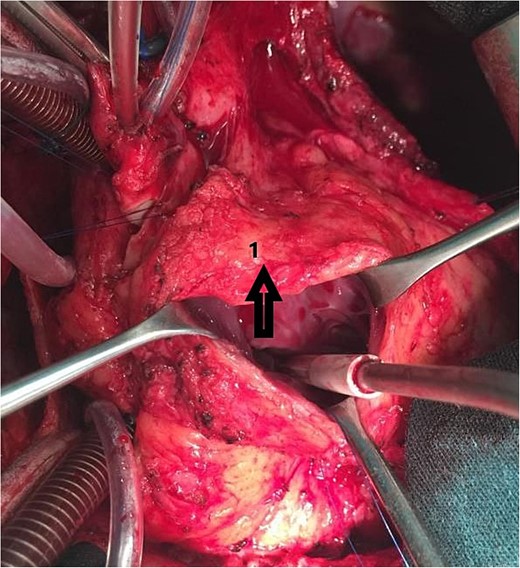

An 11-year-old girl was referred to our hospital with a main complaint of progressive exertional dyspnea. She had undergone surgical repair of SAS 6 years ago. Transthoracic echocardiogram (TTE) revealed the following findings: severe left ventricular hypertrophy, tunnel-like fibromembranous subaortic stenosis with a length of 10 mm, a peak gradient (PG) across the LVOT of 170 mmHg, and mild aortic regurgitation. Based on these findings, the patient was scheduled for elective surgical repair with a possible indication for MKO. The operation was performed via median sternotomy with great caution to avoid inadvertent rupture of any cardiac cavity due to heavy adhesions from the previous operation. The aorta was cannulated just below the takeoff of the innominate artery. Bicaval cannulation was performed to provide a bloodless field. Aortic cross-clamping was applied, and antegrade cold blood cardioplegic solution was administered via a catheter placed in the ascending aorta. The ascending aorta was opened transversely 1 cm above the sinotubular junction (Fig. 1). The aortic valve leaflets were examined carefully to confirm that the aortic valve could be preserved. LVOT was examined thoroughly, and it was clear that the stenosis in the subaortic area was so complex that simple resection through the aortic valve orifice would not be sufficient. The right ventricular outflow tract was opened transversely below the pulmonary valve. The conal papillary muscle was identified (Fig. 2). A right-angle instrument was introduced through the aortic orifice into the interventricular septum, and the tip of the instrument was used to perforate the conal septum to the left of the conal papillary muscle to prevent damage to the conduction system; the septal incision was completed with great caution to avoid damage to the aortic cusps and to extend the incision downward as necessary to completely relieve the stenotic subaortic area (Fig. 3). Interrupted 5/0 Prolene sutures were placed circumferentially around the septal incision to close the interventricular septal defect using a bovine pericardial patch to provide adequate widening of LVOT (Fig. 4). The right ventriculotomy was closed with a second bovine pericardial patch to avoid any possible obstruction of the right ventricular outflow tract (Fig. 5). The remainder of the operation was completed uneventfully. After 6 hours of mechanical ventilation, the patient was extubated, and she convalesced well postoperatively. TTE showed excellent results of the operation with PG across LVOT of 20 mmHg. On 1 year follow-up, the patient was asymptomatic and in very good general condition, and TTE findings confirmed the excellent result.

Intraoperative image showing the right ventriculotomy (2) and the conal papillary muscle (1).